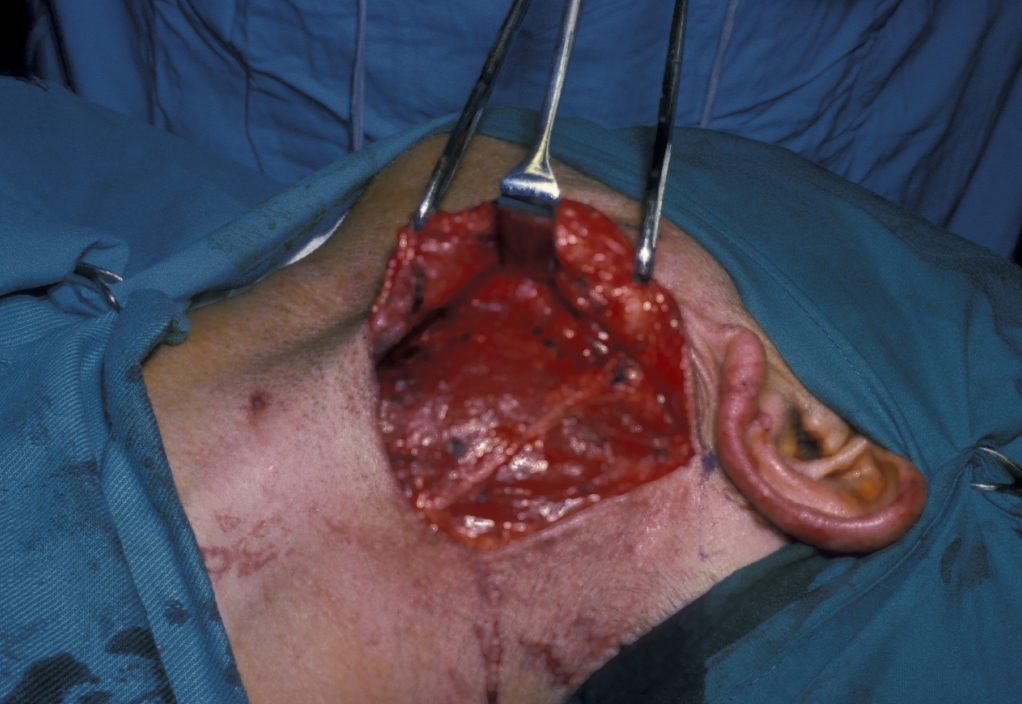

Figure 16 illustrates the distortion of the sternomastoid muscle by a branchial cyst, Figure 17 shows a branchial cyst being removed from beneath the sternomastoid muscle.

Figure 16: Skin flap elevated to show the distortion of sternomastoid caused by a branchial cyst and the preserved great auricular nerve.